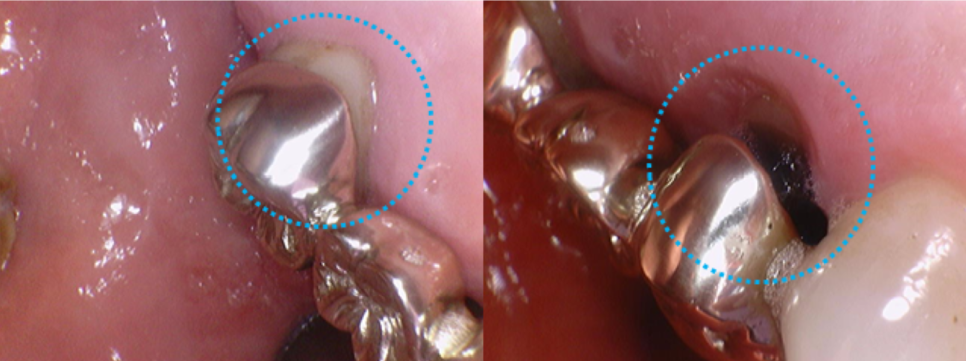

파노라마 엑스레이로 보면 보철물 주변이 검게 충치가 깊게 생긴 것을 볼 수 있습니다.

구강카메라로 찍은 사진을 보면

큰어금니는 잇몸이 내려가면서 경계부위가 떠 있고,

작은 어금니는 충치가 완전히 심하게 진행되어 까맣게 보입니다.

골드 브릿지를 제거하고 치아상태를 확인해보니,

작은어금니의 상태는 더 좋지 않아 보였고, 큰 어금니의 상태는 그나마 괜찮았습니다.